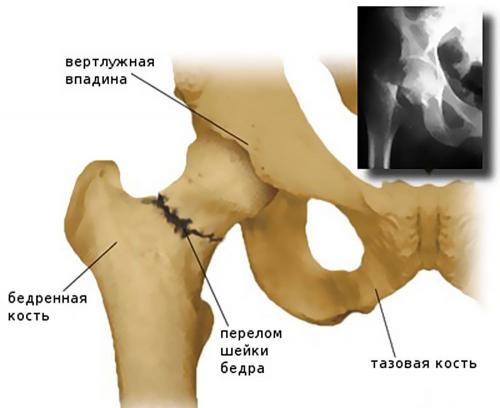

Перелом шейки бедренной кости – травма, сопровождающаяся нарушением целостности разной степени тяжести самой тонкой части бедренной кости, соединяющей ее тело с головкой. Головка бедра имеет округлую форму и является частью одного из самых крупных и мощных суставов человеческого тела – тазобедренного.

Тазобедренные суставы представляют собой парные шарнирные соединения, рассчитанные на комбинированные механические нагрузки. Каждый из них формируется бедренной костью, которая соединяется с имеющей чашеобразную форму вертлужной впадиной таза своей головкой. Вокруг вертлужной впадины расположен суставный хрящ. Он также окружает головку бедренной кости и укрепляет тазобедренный сустав. От верхушки головки бедренной кости к центру вертлужной впадины идет тонкая связка, через которую проходит артериальный кровеносный сосуд.

Отходящая от головки бедренной кости шейка располагается под углом около 120° к телу и соединяет ее с телом бедренной кости, формирующей основу бедра. За ней расположены большой и малый вертел, к которым крепятся мышцы и суставная капсула. Таким образом, шейка бедра расположена внутри суставной полости и прикрыта суставной капсулой, но не имеет надкостницы, которая в остальных случаях обеспечивает питание костной ткани. Ее питание организовано за счет артерий, проникающих в кость по нижнему краю суставной капсулы и в углубления между вертелами.

Перелом шейки бедра может произойти на любом ее участке. Конкретное его положение имеет большое значение для оценки прогноза и определения тактики лечения, поскольку, чем ближе он находится к головке, тем выше риск развития ее некроза. Таким образом, в зависимости от уровня расположения перелома различают:

- Базисцервикальные – линия перелома находится на переходе шейки бедра в ее тело. Они срастаются значительно лучше других видов переломов шейки бедренной кости.

- Трансцервикальные – шейка сломана в наиболее узкой своей части (центральной).

- Субкапитальный – перелом располагается на границе между головкой и шейкой. Он имеет наименее благоприятный прогноз.